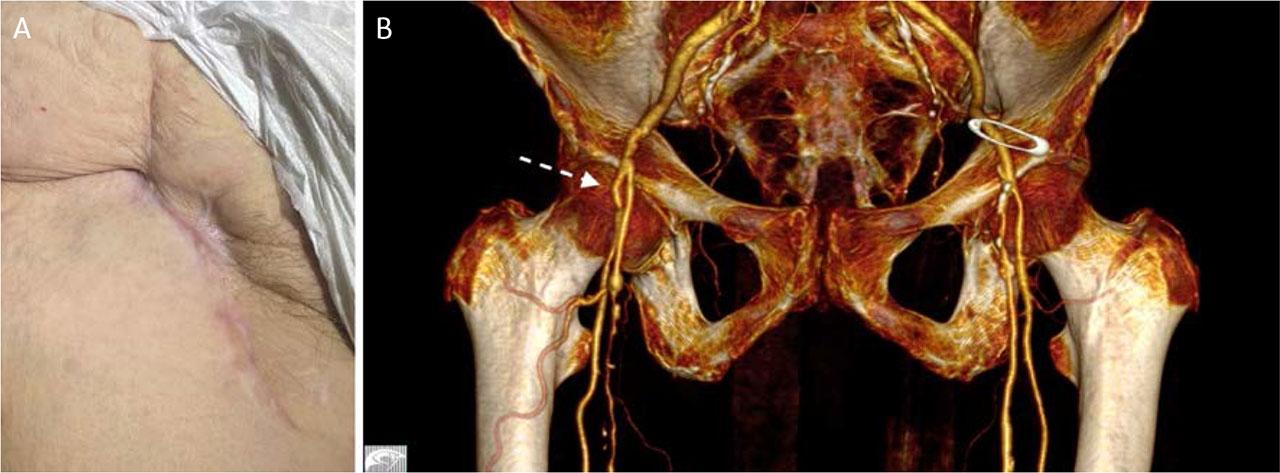

On the seventh postoperative day, the patient was discharged in good general condition, with no evidence of infection, palpable right femoral pulses, and complete remission of symptoms. At the 6-month follow-up, CTA demonstrated patent femoral arteries without thrombus or right inguinal hematoma, and complete tissue healing (Figure 6).

Clinical appearance (A) and 3D CTA reconstruction (B) 1 month after surgery.